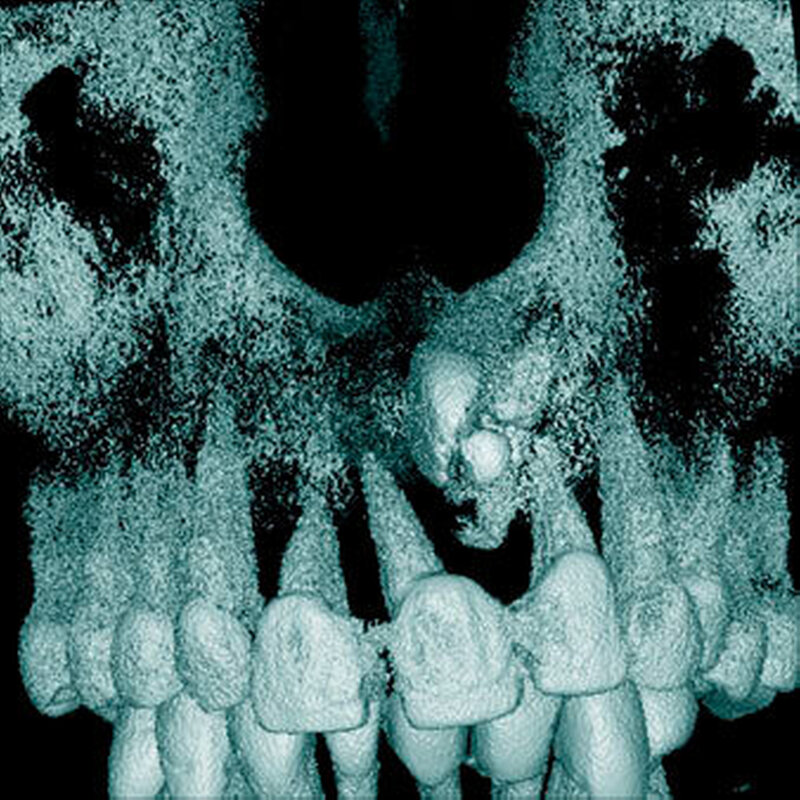

Überzählige Zähne sind die häufigste Ursache für einen unterbliebenen oder verzögerten Durchbruch der oberen Schneidezähne (Abbildungen 13, 14, 15) [Betts Camilleri, 1999]. Besonders beim höckerförmigen Typ kommt es häufig zu Störungen der Eruption der oberen Schneidezähne [Mason et al., 2000]. Diese Komplikation macht sich klinisch initial dadurch bemerkbar, dass die oberen seitlichen Schneidezähne durchbrechen und die Eruption von einem oder beiden zentralen Schneidezähnen ausbleibt [Rajab Hamdan, 2002]. Auch in anderen Lokalisationen der Kiefer können überzählige Zähne zu Durchbruchsstörungen benachbarter Zähne führen [Garvey et al., 1999; Rajab Hamdan, 2002; Mossaz et al., 2014]. Insgesamt liegt die Prävalenz für den Ausfall des Durchbruchs bleibender Zähne bedingt durch überzählige Zähne zwischen 10,2 Prozent und 61 Prozent [Tay et al., 1984; Koch et al., 1986; Tyrologou et al., 2005; Fernández Montenegro et al., 2006; Liu et al., 2007; Gündüz et al., 2008; Hyun et al., 2009; Mínguez-Martinez et al., 2012; Mossaz et al., 2014].

Überzählige Zähne werden nach ihrer Lage im Zahnbogen und auch aufgrund ihrer Morphologie eingeteilt. Basierend auf der Lage unterscheidet man bei überzähligen Zähnen zwischen Mesiodens (Oberkiefer median), zwischen den zentralen Inzisiven (Abbildungen 5 und 6), einem zusätzlichen Schneidezahn (zentral oder lateral), Eckzahn, Prämolar (Abbildung 7), Paramolar und Distomolar (Abbildungen 8). Mesiodentes werden am häufigsten dia- gnostiziert, wobei Prozentsätze zwischen 38,8 Prozent bis 86,3 Prozent der überzähligen Zähne in der Literatur zu finden sind [Salcido-García et al., 2004/38,8 Prozent, Fernández Montenegro et al., 2006 /46.9 Prozent; Mossaz et al., 2014/48.5 Prozent; Ferrés-Padró et al., 2009/53.2 Prozent; Schmuckli et al., 2010/75 Prozent; Rajab Hamdan 2002/83.2 Prozent; Liu et al., 2007/86.3 Prozent]. Überzählige Prämolaren und seitliche Schneidezähne sind die zweithäufigste Gruppe der überzähligen Zähne. Überzählige Eckzähne, Paramolaren und Distomolaren dagegen gelten als eher selten [Rajab Hamdan, 2002; Salcido- García et al., 2004; Liu et al., 2007; Ferrés-Padró et al., 2009; Schmuckli et al., 2010; Mossaz et al., 2014]. Einzig eine Spanische Gruppe [Fernández Montenegro et. al., 2006] berichtete, dass Paramolaren und Distomolaren insgesamt relativ häufig seien (18 Prozent, beziehungsweise 5,6 Prozent). Überzählige Zähne kommen im Ober- und Unterkiefer vor, wobei sich überzählige Schneidezähne in der Regel im Oberkiefer, überzählige Prämolaren sich dagegen eher im Unterkiefer befinden [Fernández Montenegro et al., 2006; Ferrés-Padró et al., 2009; Mossaz et al., 2014]. Überzählige Molaren wiederum treten normalerweise im Oberkiefer auf [Cassetta et al., 2014; Kaya et al., 2014].

Bei überzähligen Zähnen werden vier morphologische Typen unterschieden: konisch (Abbildung 9), tuberkulär (höckerförmig; Abbildung 10), überzählige Zähne mit identischer Zahnform (Abbildung 11) und Odontom (Abbildung 12) [GARVEY et al. 1999]. Der konische überzählige Zahn ist ein kleiner, zapfenförmiger Zahn und zudem der häufigste Fall im bleibenden Gebiss [Rajab Hamdan 2002, Liu et al. 2007, Gündüz et al., 2008; Ferrés-Padró et al., 2009; Hyun et al., 2009; Schmuckli et al., 2010; Mossaz et al., 2014]. Er kommt oft zwischen den oberen zentralen Schneidezähnen vor und entwickelt sich gleichzeitig zur Wurzelbildung der bleibenden Schneidezähne. Konische überzählige Zähne führen meist nicht zu einer Durchbruchstörung oder -behinderung der zentralen Schneidezähne. Tuberkuläre, überzählige Zähne sind größer als der konische Typ und besitzen einen zusätzlichen charakteristischen Höcker oder Tuberkel der Zahnkrone. Sie kommen oft gepaart vor und liegen in der Regel palatinal der oberen mittleren Schneidezähne. Im Gegensatz zu konischen überzähligen Zähnen brechen die meisten tuberkulären nicht in die Mundhöhle durch und es kommt nicht selten zur Durchbruchstörung oder -behinderung der zentralen Schneidezähne [Mason et al., 2000; Minguez-Martinez et al., 2012]. Überzählige Zähne mit identischer Zahnform sind Zähne, welche vom eigentlichen Zahn in der Lage (also in der Zahnreihe gelegen) und Form nicht zu unterscheiden sind.